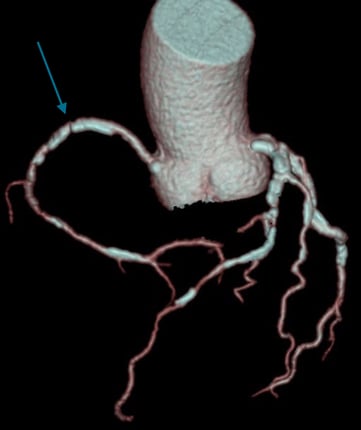

Example of a sufficiently good examination. Good contrast in the coronary arteries. The heart is displayed without steps.

Another example after 3D post-processing (obligatory vessel and volume display): The coronary vessels are clearly and continuously displayed. Image source: Rolf et al. 2023